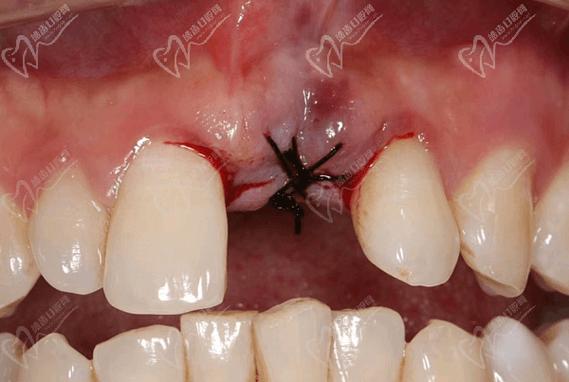

(图片来源网络,侵删)- 组织愈合反应: 拆线时可能会对伤口周围的软组织(牙龈)造成轻微刺激或牵拉,引起短暂的疼痛或不适,拆线后几天内,牙龈和骨头仍在愈合过程中,轻微的胀痛、钝痛或对冷热敏感是常见的。

- 炎症消退期: 手术区域的炎症可能尚未完全消退,拆线后局部血液循环变化或轻微刺激可能引发疼痛。

- 线头刺激: 拆线时可能有线头残留或对牙龈有轻微刺激感,引起局部疼痛。